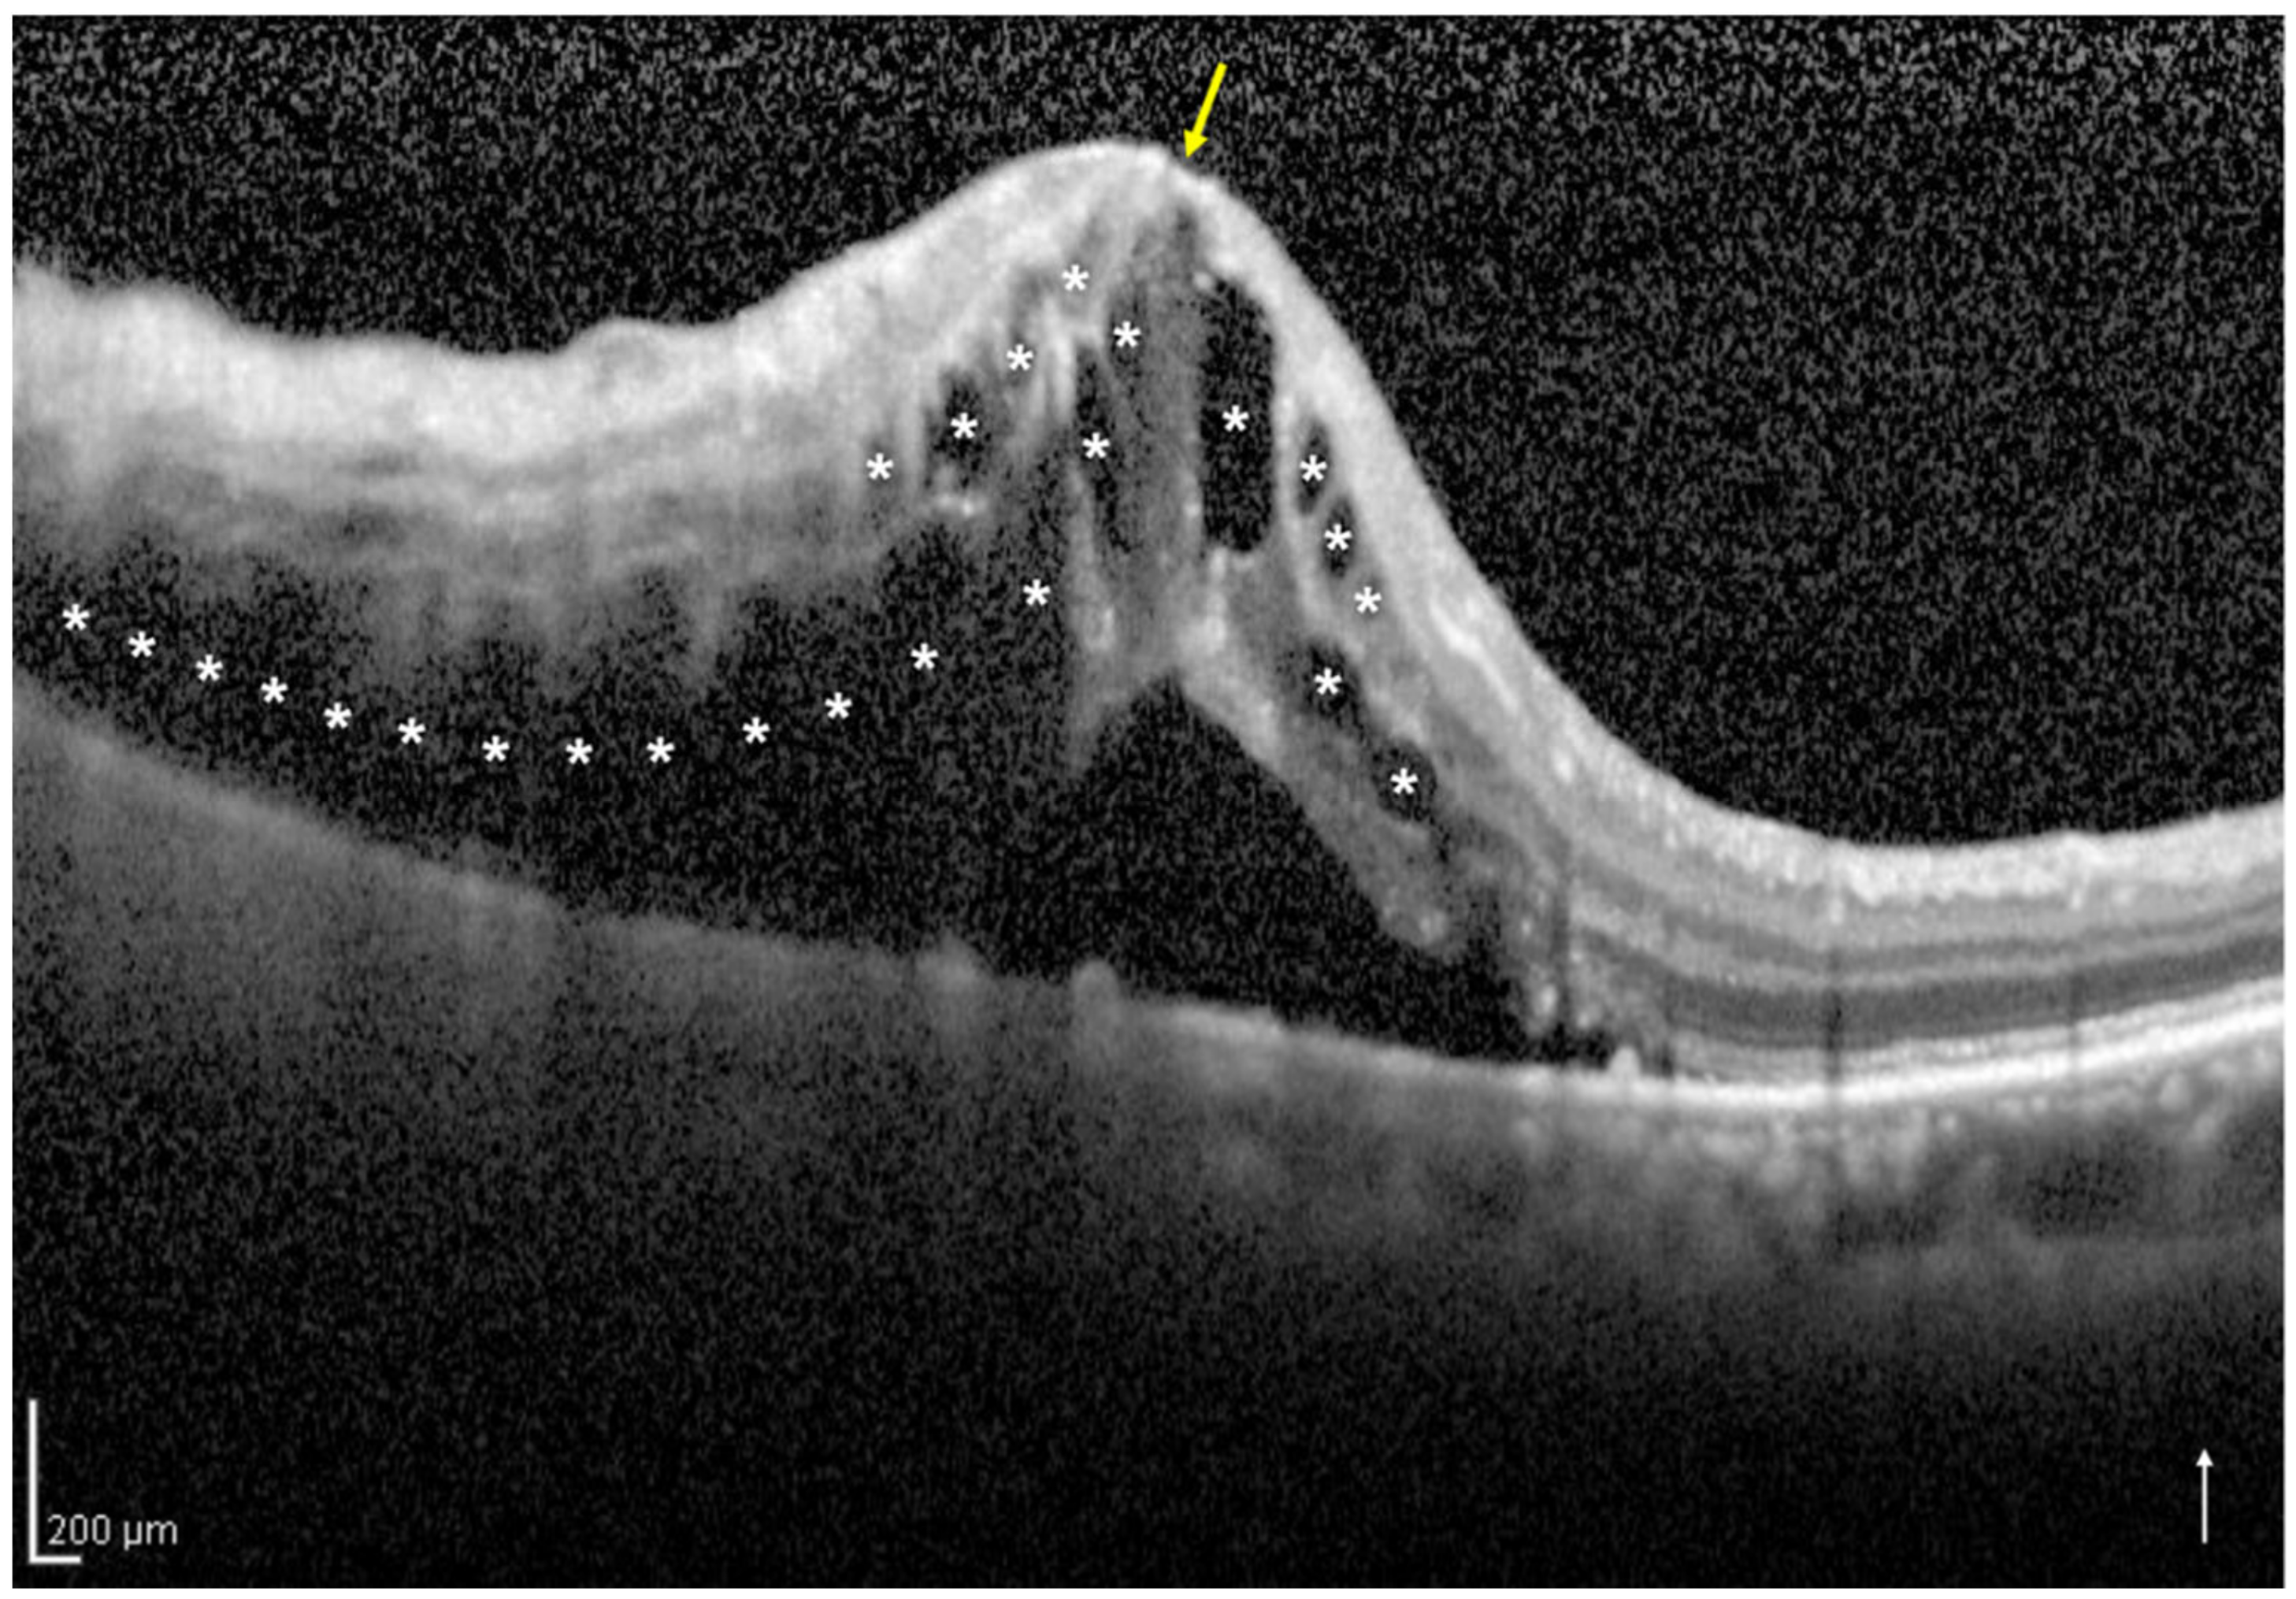

Based on the vertical OCT B-scan image through the fovea at the initial visit, we classified the eyes into two groups: the one-side IRF group included eyes with IRF not involving the central foveola (Figure 1), and the both-sides IRF group included eyes with IRF involving the central foveola (Figure 2). If the vertical OCT B-scan detected subretinal fluid (SRF) involving the central foveola with the IRF not involving the central foveola, the eyes were classified into the one-side IRF group in the present study. Two retinal specialists (H.S. and H.I.) independently classified the eyes included in the two groups and were masked to the BCVA at the initial and 12 months visits and other patient information related to the eyes; a senior observer (M.Z.), who was also blinded to the patient data, made the final decision concerning the classification in case of disagreement.

Figure 2.

A vertical optical coherence tomography (OCT) image of the right eye with intraretinal fluid (IRF) involving the central foveola secondary to branch retinal vein occlusion of an 85-year-old woman. The OCT image shows IRF (asterisks) involving the central foveola (yellow arrow) and subretinal fluid. The white arrow indicates the OCT scan direction. This eye was classified into the both-sides IRF group.